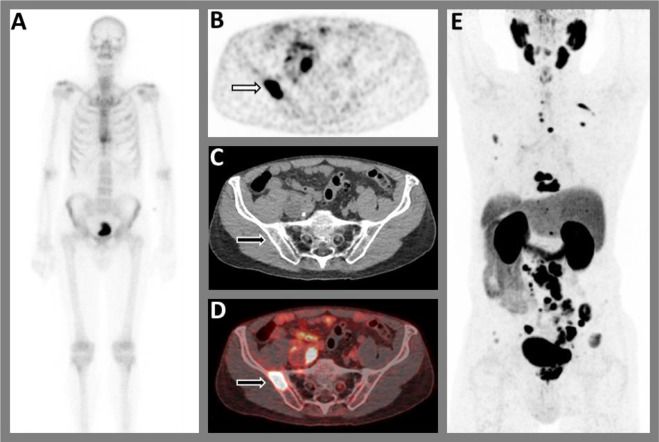

What To Do With a Positive PSMA PET and Negative Conventional Imaging in Patients With Prostate Cancer

Is PSMA PET/CT More Beneficial than Bone Scintigraphy in Detecting

Guiding management of therapy in prostate cancer: time to switch

PSMA-PET is rapidly changing the standard of care for prostate

Guiding management of therapy in prostate cancer: time to switch

Sequencing of Conventional and PSMA-PET Imaging in Prostate Cancer